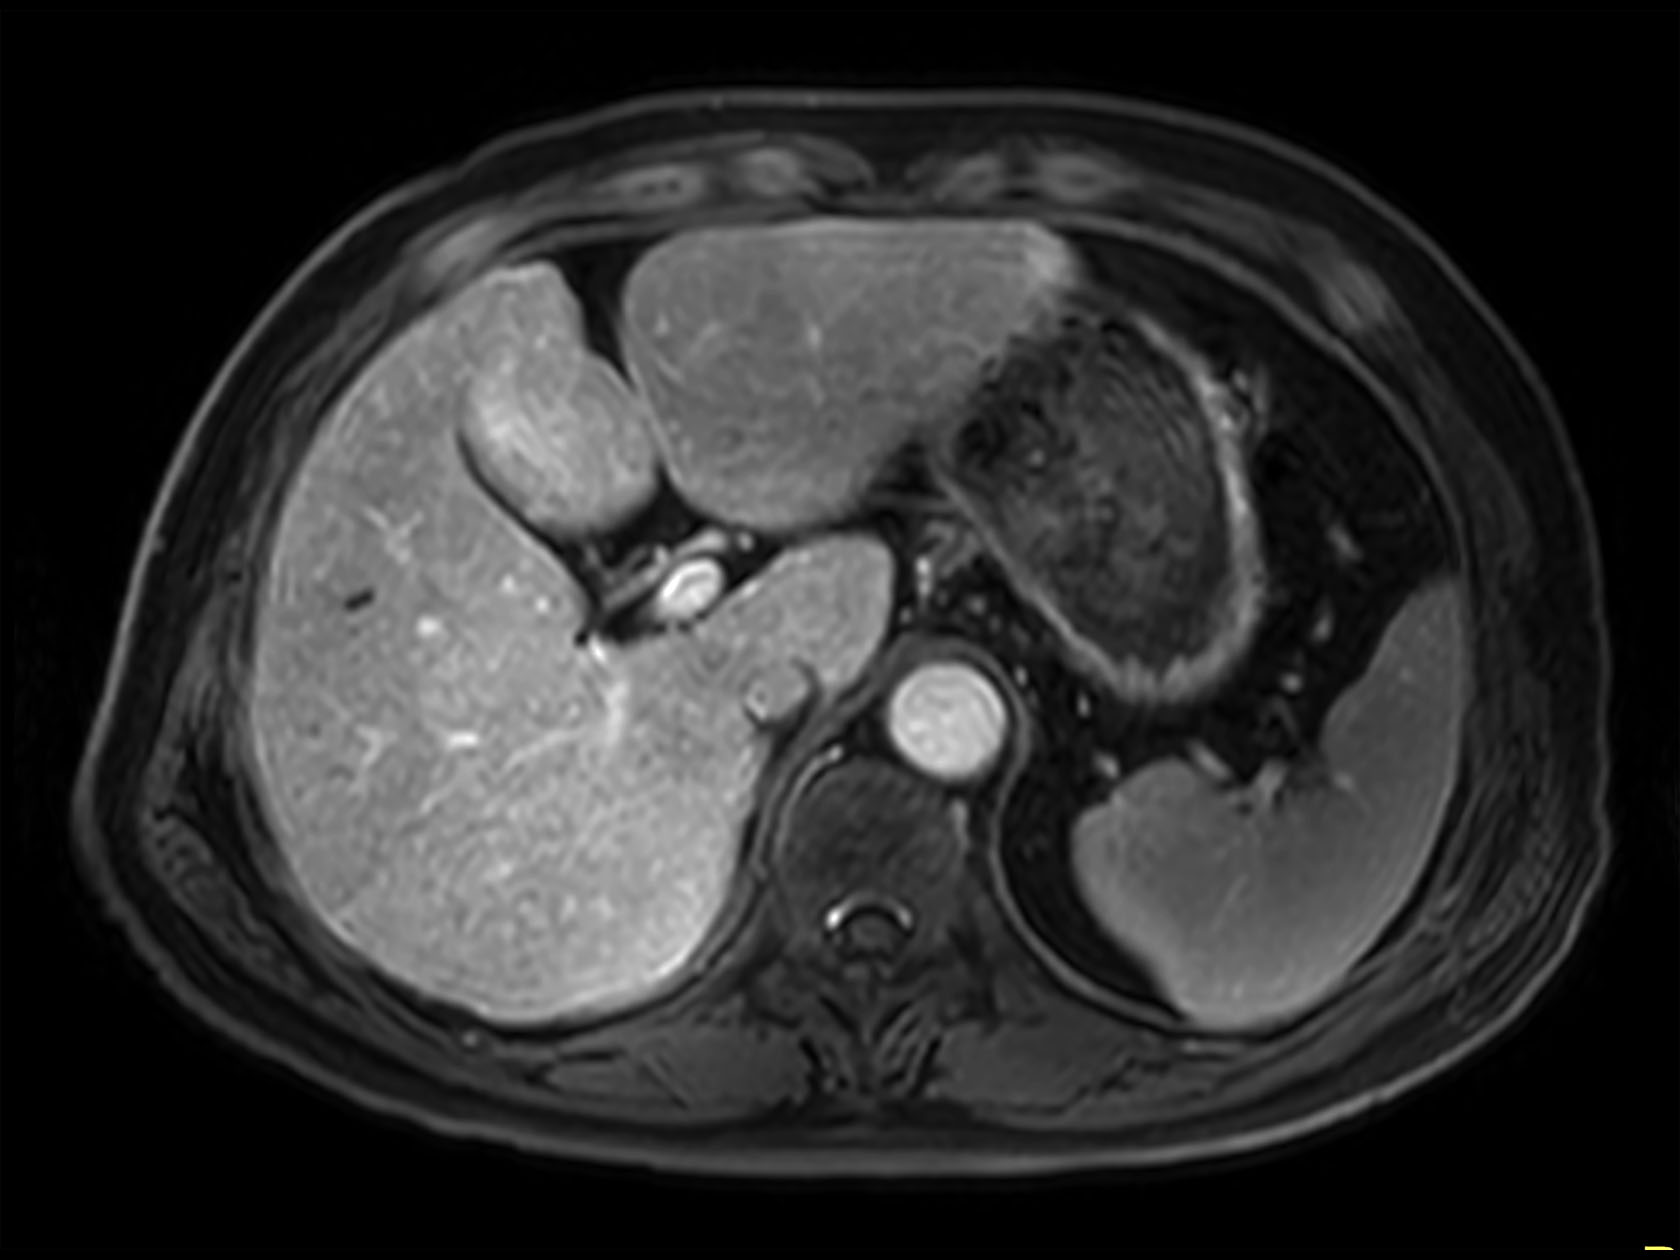

dyn mDIXON XD FFE  (post gado, arterial phase)